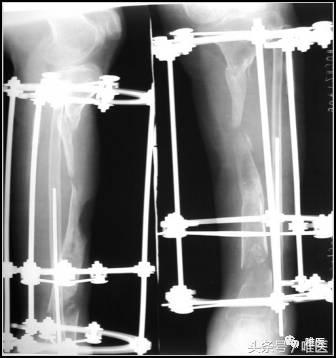

一期:左胫骨全环外架固定,远端截骨,术后骨段逐渐滑移,克服骨缺损。

(3)骨段搬移

是治疗节段骨缺损较理想的方法。

先一期截骨,使用外固定架进行骨段滑移。